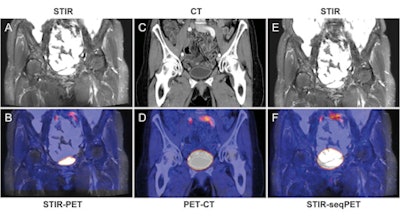

Bladder of a 65-year-old female patient. Images illustrate improved alignment with simultaneous PET/MRI (A, coronal STIR; B, fused images) compared to sequential PET/CT (C, coronal CT; D, fused images) and retrospective fusion of PET and MRI (E, coronal STIR; F, fused images). Images courtesy of Radiology.

Bladder of a 65-year-old female patient. Images illustrate improved alignment with simultaneous PET/MRI (A, coronal STIR; B, fused images) compared to sequential PET/CT (C, coronal CT; D, fused images) and retrospective fusion of PET and MRI (E, coronal STIR; F, fused images). Images courtesy of Radiology.For all thoracic regions, the amount of misalignment was similar, according to Brendle and colleagues. Mean cumulative misalignment was 10.1 mm (± 7.7) in the right lung, 11.0 mm (± 8.4) in the left lung, and 12.0 mm (± 9.2) in the mediastinum.